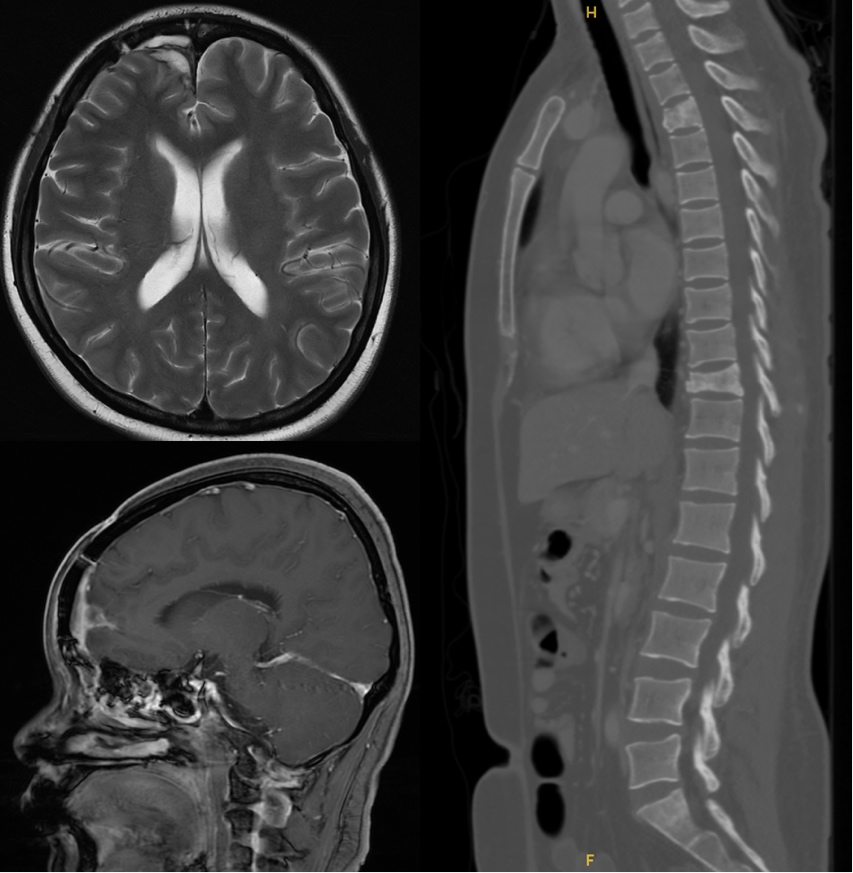

2025年5月胸腹盆CT及全脊柱MRI

脊柱多发转移瘤(T3、T10、L3椎体及附件,其中T10椎体合并病理性骨折)。左乳、肺、肝等未见明显异常。

目前“卡培他滨+曲妥珠单抗+吡咯替尼”方案已维持治疗6个月,仍在持续治疗中。定期影像学复查显示全身骨病灶稳定,颅内及颅外无肿瘤新发进展征象。患者一般情况好,血常规基本维持正常。